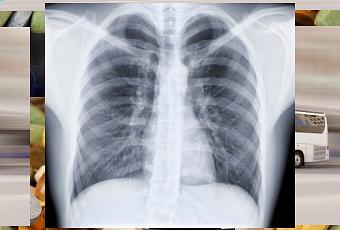

France - Un nouvel outil mathématique permet de déterminer l’âge des poumons, souvent différent de l'âge réel. Un moyen efficace pour dépister une broncho-pneumopathie chronique obstructive (BPCO).

Il est prouvé que les poumons d’un fumeur vieillissent plus vite que la normale. Avec l’outil BPCO-6, la différence entre âge biologique et âge pulmonaire peut être mesurée et ainsi alerter le médecin sur le risque de BPCO de son patient.

Le Pr Roche, pneumologue à l’Hôtel-Dieu de Paris, explique que les poumons vieillissent de façon naturelle avec l’âge, mais que le tabac accélère ce vieillissement : « Vous pouvez très bien avoir 45 ans mais un âge pulmonaire de … 70 ans ! » Ce vieillissement prématuré est le signe d’une BPCO, maladie qui diminue progressivement la capacité respiratoire.

Actuellement les dépistages ont lieu souvent trop tard, avec le risque de survenue d’insuffisance respiratoire grave. Avec BPCO-6, un dépistage précoce permettra une prise de mesures rapides, à commencer par un arrêt du tabac et, ainsi, une limitation réelle des risques vitaux.